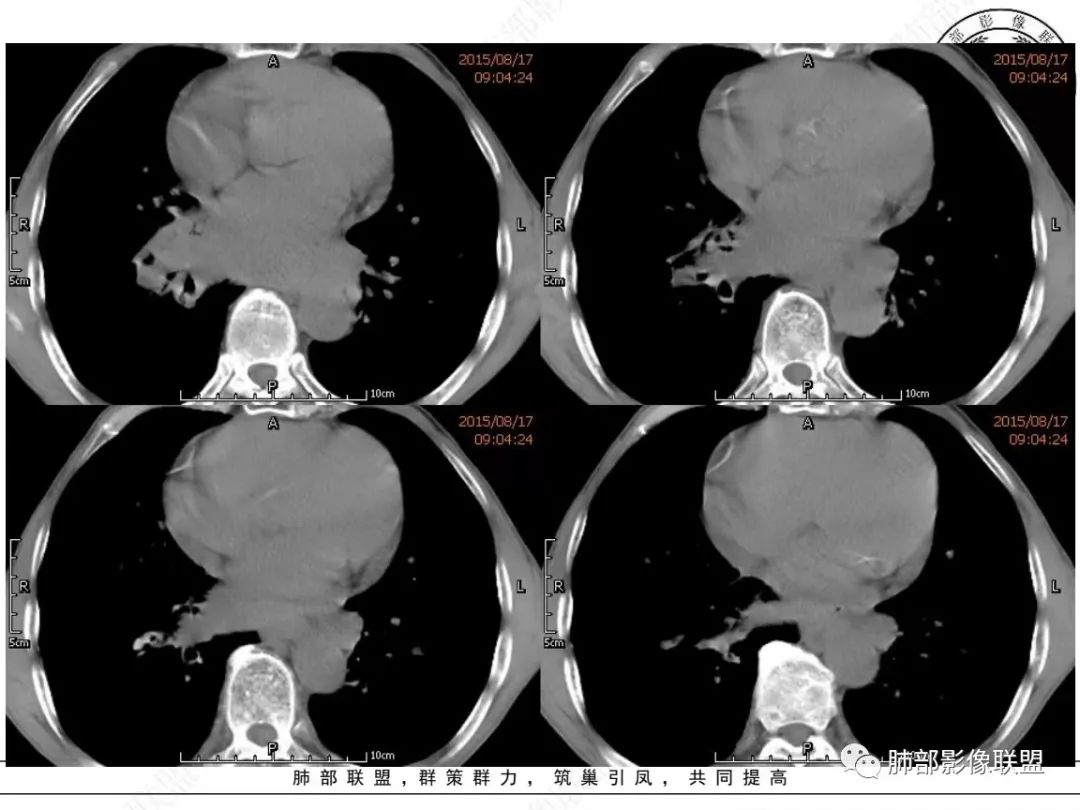

谢加平:纵隔内中后纵隔及右肺门淋巴结肿大,形成大肿块,整体密度均匀,并轻度强化,见“血管飘浮”征,包绕气管分叉及右主支气管及中间段支气管明显受压狭窄,并包埋右肺门血管束,无侵蚀破坏,右肺动脉后壁见压迹影,右肺下叶背段有阻塞性炎症,首选淋巴瘤,支气管超声内镜活检,明确诊断!

理由:四点,1、整个病灶位于纵隔中央后主,且以后纵隔为主,2、病灶内血管漂浮,3、肺内无原发灶,没找到“娘”。4、颌下淋巴结穿刺未找到小细胞癌。所以肯定先考虑淋巴瘤。

我想CT上,侵袭力强也是特征,破坏力弱表现在血管包绕但形态基本不变,和比较软的感觉。

另外小细胞癌中央区肿块通常没那么圆,有鸭蹼状凸起,周围也不是特别干净,常有小结节或其它阴影

MCL的CT表现为分布无规律的全身多区域淋巴结受侵,少有单一区域淋巴结受累,结外器官受侵多见;MCL有一般NHL淋巴结受累基本CT表现,平扫CT表现为病变密度均匀,受累淋巴结区内呈融合状生长,边界清楚,增强后病灶呈均匀、中等强化,一般病变内无低密度坏死区。确诊需要病理及免疫组化,根据肿瘤组织形态学和免疫组织化学 CD5 及cyclin D1 的表达绝大多数 MCL 可做出明确病理诊。

1.小细胞肺CA:好发吸烟老年男性。常有血液NSE及胃泌素释放肽前体升高。Syn、CgA、CD56阳性。其CT特点可有:冰冻纵隔、冰冻肺门。血管包埋征。针尖样支气管。鸭蹼状凸起。娘小崽大。脂肪间隙消失(常指纵隔及肺门内)。阻塞性炎症不重。侵袭性强。破坏力不强。收缩力弱,内无空泡。沼泽样强化,坏死散而小,坏死不彻底,强化偏低。表面圆钝,角状及条状凸起,蠕虫样表现,腊肠样尾巴(朝肺门侧或背离肺门侧均可以)。胸水多“清澈”(可以理解为淋巴液回流障碍导致的胸水)。点簇状钙化(类似盐与胡椒样)。多见癌性淋巴管炎。另外黄勇老师提出胸膜下的小细胞肺癌具有“山丘征”的特点。